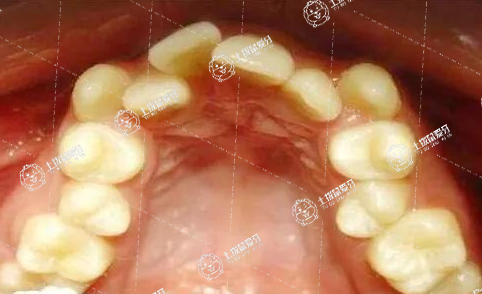

牙列擁擠的矯治步驟和大多數(shù)錯(牙合)畸形的矯治步驟是一樣的,主要包括前期的準(zhǔn)備過程。要先檢查口內(nèi)情況,并拍攝相應(yīng)X光片,了解牙齒在骨頭里的情況以及上下頜骨的情況,然后進(jìn)行取模、拍照。

現(xiàn)在牙齒錯頜畸形,在兒童發(fā)育階段的廣泛存在。很多的患兒都存在牙齒排列不齊、里出外進(jìn),有些還存在更嚴(yán)重的比如反頜、上下頜前突畸形。家長關(guān)心牙齒矯正的最佳年齡,在討論最佳年齡的時候,首先要分析牙齒錯頜的類型、程度和病因。對于一般意義上的牙齒錯頜畸形,也就是最常見的牙齒排列不齊、里出外進(jìn),認(rèn)為最佳的矯正年齡是在十二三歲。乳牙完全脫落、恒牙完全萌出、恒牙裂剛剛要建合,這個階段進(jìn)行矯正最佳。孩子配合度好,同時小孩的頜骨改建能力強(qiáng),牙齒的移動速度可以更好,這種情況下做牙齒矯正速度合適、矯正的效果好,帶來的并發(fā)癥還比較少。這是指一般意義的錯頜畸形,一般選擇十二三歲替牙期結(jié)束以后進(jìn)行。